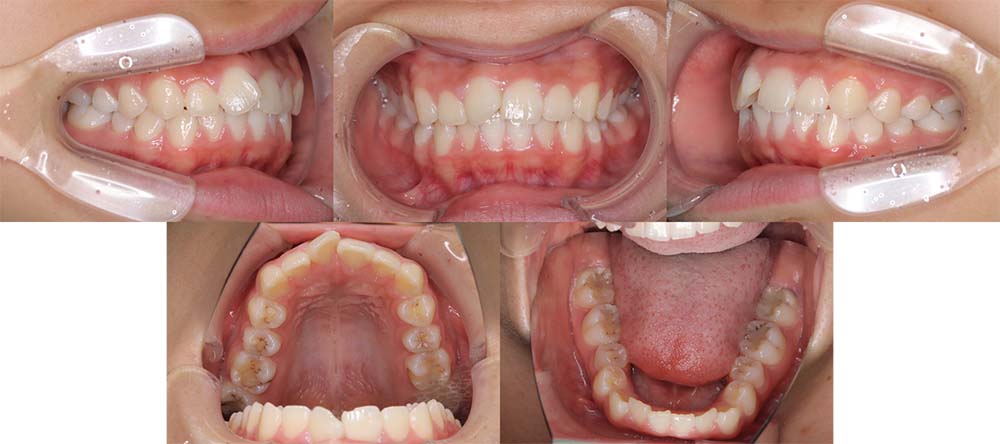

| 症例分類 | 上下顎前突、口唇突出 |

| 診断名 | 口唇突出を伴う上下軽度叢生 |

| 主訴 | 前歯が気になる |

| 年齢 | 15歳8ヶ月 |

| 性別 | 女性 |

| 抜歯部位 | 上下左右の第一小臼歯(4本) |

| 使用装置 | 表側のワイヤー装置 |

| 治療期間 | 1年9ヶ月 |

| 保定装置 | 固定式保定装置、取り外し式保定装置(8時間) |

| 費用 | [検査・診断料] ¥49,500 [基本施術料] ¥792,000 [調整料] ¥4,400/回 [抜歯] ¥5,500/本 [保定装置] ¥55,000(税込) 抜歯や虫歯治療は他院にて費用が別途かかります。(抜歯¥4,000〜10,000/本)

当初は前歯のガタガタを気にされており、上顎の部分治療を希望されました。しかしながら、上顎前歯の叢生のみの改善は可能だが、口唇突出感はなくなり、口が自然に閉じるようにするためには抜歯が必要なことを説明したところ、抜歯して治療することを希望されました。

上下第一小臼歯を抜去して表側のマルチブラケット装置で治療しました。顎間ゴムの協力度が良く予定より早く治療が終了することができました。

口唇突出感をなくし、しっかりと咬合することができました。